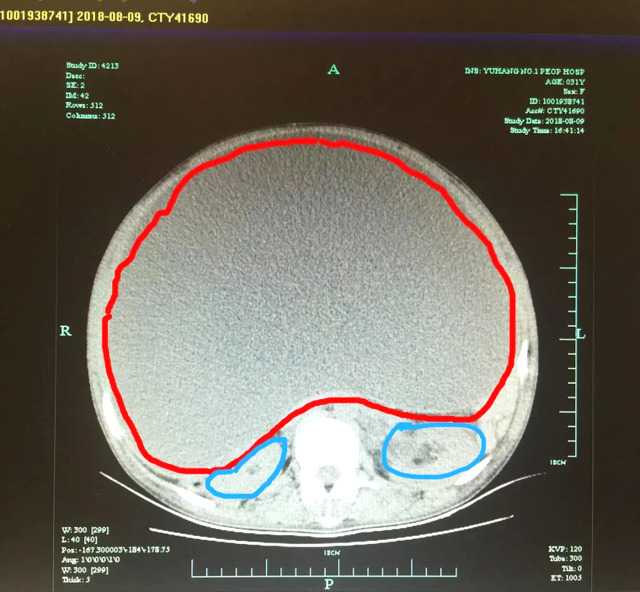

杭州小姑娘说自己没结婚、没男友!肚子却越来越大?